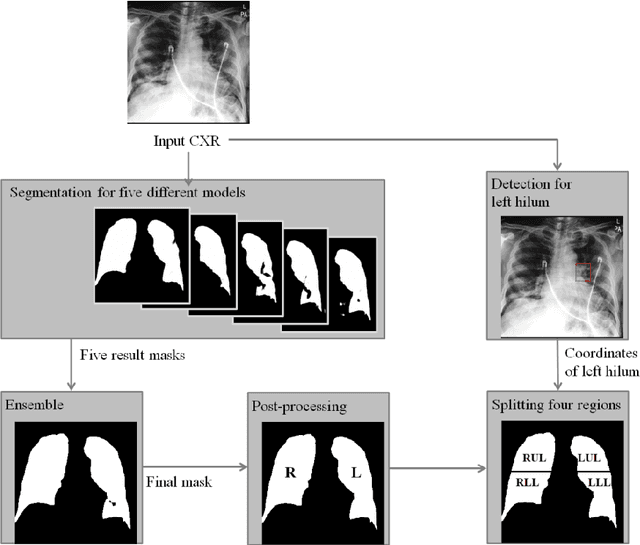

Abstract:Purpose. Imaging plays an important role in assessing severity of COVID 19 pneumonia. However, semantic interpretation of chest radiography (CXR) findings does not include quantitative description of radiographic opacities. Most current AI assisted CXR image analysis framework do not quantify for regional variations of disease. To address these, we proposed a four region lung segmentation method to assist accurate quantification of COVID 19 pneumonia. Methods. A segmentation model to separate left and right lung is firstly applied, and then a carina and left hilum detection network is used, which are the clinical landmarks to separate the upper and lower lungs. To improve the segmentation performance of COVID 19 images, ensemble strategy incorporating five models is exploited. Using each region, we evaluated the clinical relevance of the proposed method with the Radiographic Assessment of the Quality of Lung Edema (RALE). Results. The proposed ensemble strategy showed dice score of 0.900, which is significantly higher than conventional methods (0.854 0.889). Mean intensities of segmented four regions indicate positive correlation to the extent and density scores of pulmonary opacities under the RALE framework. Conclusion. A deep learning based model in CXR can accurately segment and quantify regional distribution of pulmonary opacities in patients with COVID 19 pneumonia.